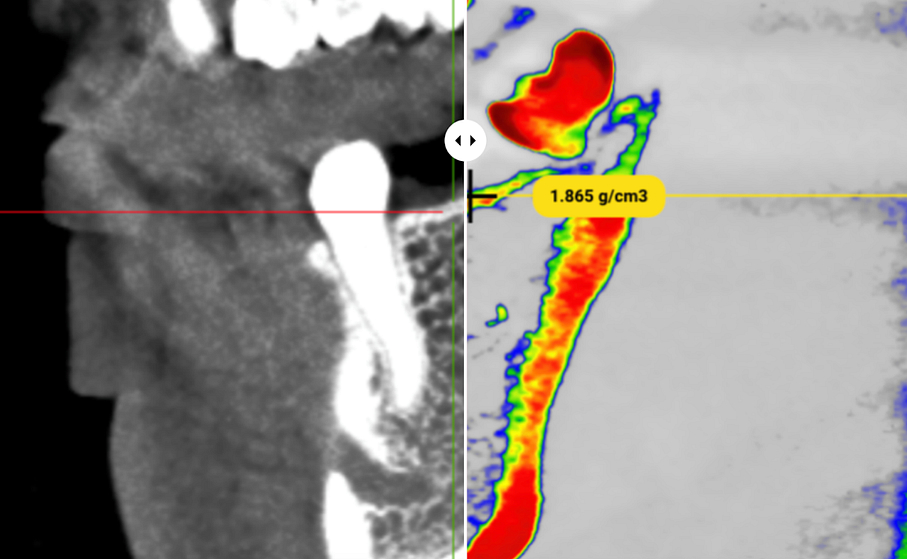

SimDensity - AI-Powered Bone Density Analysis

Visual Tech-lab showcased their SimDensity platform at IDS 2025, offering a AI-powered bone density measurement technology using existing CBCT data with a proprietary bone density phantom standard.

The technology analyzes CBCT scans to provide quantitative bone density measurements particularly valuable for pre-operative implant planning. Beyond implantology, SimDensity offers applications in orthodontic treatment planning for both clear aligner and traditional bracket systems, helping identify potential limitations or considerations related to bone density before initiating tooth movement.

What makes the system particularly practical is its seamless integration with existing CBCT technology without requiring additional patient radiation exposure. The cloud-based platform approach allows for implementation without significant hardware investments or workflow disruptions.

SimDensity represents another example of how artificial intelligence is extracting more clinical value from existing diagnostic imaging, providing quantitative data points that enhance evidence-based treatment decisions and potentially improve predictability of outcomes.